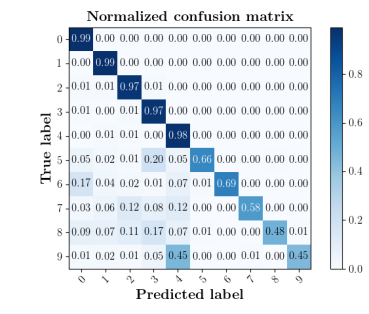

We further compare the performance of MIDNet with and without unlabeled data on the target domain. Here, the with unlabeled data setting utilizes the training data containing labeled data and unlabeled data, while the without unlabeled data setting only uses the labeled data. The confusion matrices in Fig. 8(a) show the effectiveness of unlabeled data in the proposed method, for example, the classification accuracy of in MIDNet (e.g., 4CH and Lips) improves when integrating unlabeled data.

The confusion matrices in Fig. 8(b) show the effectiveness of unlabeled data in the proposed method. The classification accuracy of Femur and Lips in MIDNet improves when using unlabeled data.

We further compare the performance of MIDNet in a semi-supervised setting and a fully-supervised setting. Here, the semi-supervised setting utilizes the training data containing labeled data and unlabeled data, while the fully supervised setting only uses the labeled data. The confusion matrix in Fig. 14 shows the effectiveness of unlabeled data in our proposed method, for example, the classification accuracy of greatly improves when integrating unlabeled data (semi-supervised).